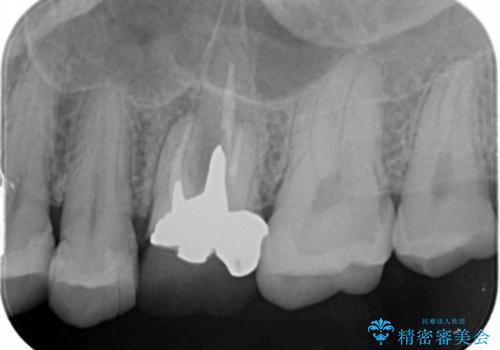

- 検査の結果、長くもたせることが困難な歯が確認された患者様です。

抜歯を行い、周囲の骨を増やしつつインプラントを埋入することとなりました。

良い位置に良い方向でインプラントを埋入することができました。